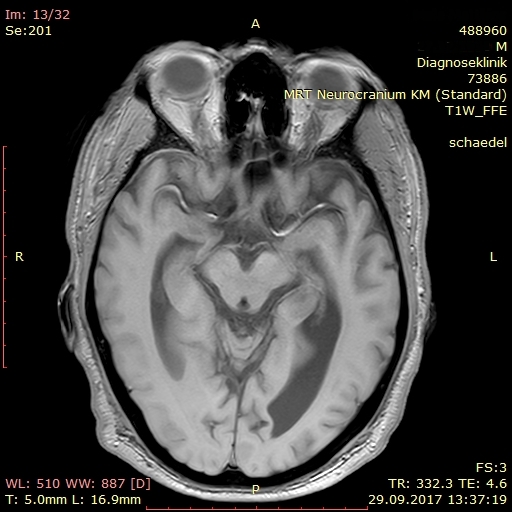

Dieser Tage erhielt ich einen erschreckenden Einblick in das Ausmaß der Zerstörung Meinerselbst durch Vater und Mutter, die beiden Mörder meiner Seele. Auf der diagnostischen Suche nach der Ursache für meinen Schwankschwindel wurde auch mein Schädel fixiert und per MRT durchleuchtet. Nach der 25minütigen Prozedur in der Röhre traf ich den Radiologen vor dem Bildschirm und sah mir scheibchenweise ins Gehirn. Der Arzt war sichtlich betroffen über die auffällige Atrophie meines Gehirns. Er zeigte mir die ungewöhnlich ausgedehnten Ventrikel, sprich Hohlräume, an den Seiten und im Innenraum meines Brägens. Er fragte nach möglichen Erkrankungen wie Diabetes und Bluthochdruck. Ich verneinte und erwähnte meine PTBS. Er erkundigte sich nach der Ursache, ich verstand die Frage akustisch nicht, meine Frau antwortete für mich: sexueller Missbrauch und Misshandlung durch die Eltern. Nun kam zu seiner Betroffenheit noch ein tieftrauriger Zug, und er erklärte mir, dass Missbrauch und Misshandlung derlei tiefe und bleibende Spuren im Gehirn hinterlassen. Angesichts meiner geistigen Präsenz zeigte er zudem über die strukturelle Regenerationsfähigkeit des Gehirns Erstaunen. – Später sah ich im Internet das „Schalenhirn“ eines Mathematikers mit einem IQ von 126, das nur geschätzte 100 g Masse besaß (siehe hier).

In meinem Therapietagebuch notierte ich dazu trocken: „Neben dieser Diagnose: keine Blutungen, keine Aneurysmata, keine Tumore oder Metastasen. Nur ein weiterer Ausschluss auf der Diagnose zum psychogenen Schwankschwindel. Die Hirnatrophie selbst ist nur ein Sachverhalt des Missbrauchs, man kann auch mit einem „Resthirn“ gescheit und sinnenfroh überleben.“

Als Hörbeispiel meiner nachhaltigen Schädigung von Angst und PTBS habe ich abschließend ein Video des Bordun Orchesters eingebettet. Die Bilder in diesem Beitrag kehren mein sichtbar zerstörtes Inneres, sprich mein Gehirn, nach außen.

kurz zu ihren schnittaufnahmen vom kopf. ich bin kein fachmann und kann damit nicht viel anfangen, obwohl ich vor vielen jahre einem oberarzt erklären musste, wir er mit schnittaufnahmen umzugehen hat. er sagte über die aufnahmen unseres jüngsten den ermutigenden satz: aber der hat ja kein gehirn. – ich habs ihm dann gezeigt. unser jüngstes kind, ein adoptivkind, kam mit einem hirnschaden zur welt, dazu gehörte der hydrozephalus (wasserkopf). ganz beiläufig hatte ich im psychologie-studium gelernt, dass man auch mit hydrozephalus beachtliche leistungen erbringen kann.